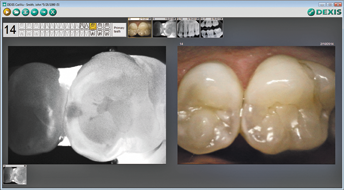

In addition to its innovative technology, CariVu is fully integrated with the DEXIS imaging software programs. Dentists are able to display the transillumination video feed or images next to previously captured X-rays and camera images, allowing for quick comparison and monitoring of areas over time. Since CariVu images are similar in appearance to familiar X-ray images, there is no need to calibrate the device or become versed in the meaning of multiple color codes or numeric indicators to find out the location and size of caries.